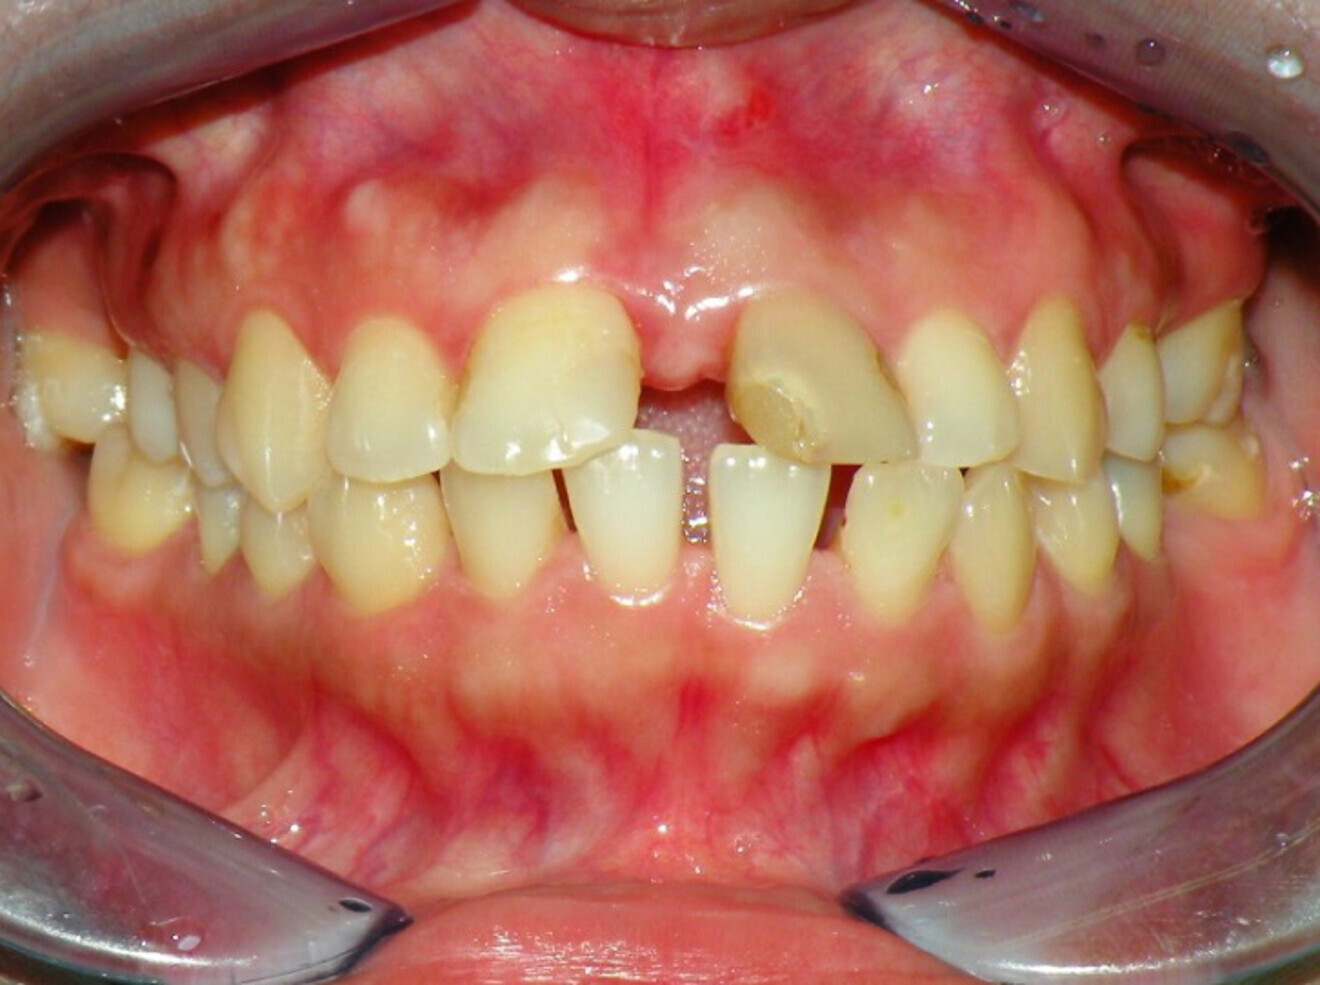

Case 2

• 50-year-old woman

• No underlying medical condition.

• Main complaint: Multiple gaps.

Intra-oral findings:

Class I malocclusion with poli diastemas in both upper and lower arch.

Overbite= 1mm Overjet = 3mm

No molar classification (absence of molars)

Panoramic radiograph analysis:

Missing 18, 16, 25,26, 28, 36, 47 and 48.

20-30% vertical bone loss upper anterior region.